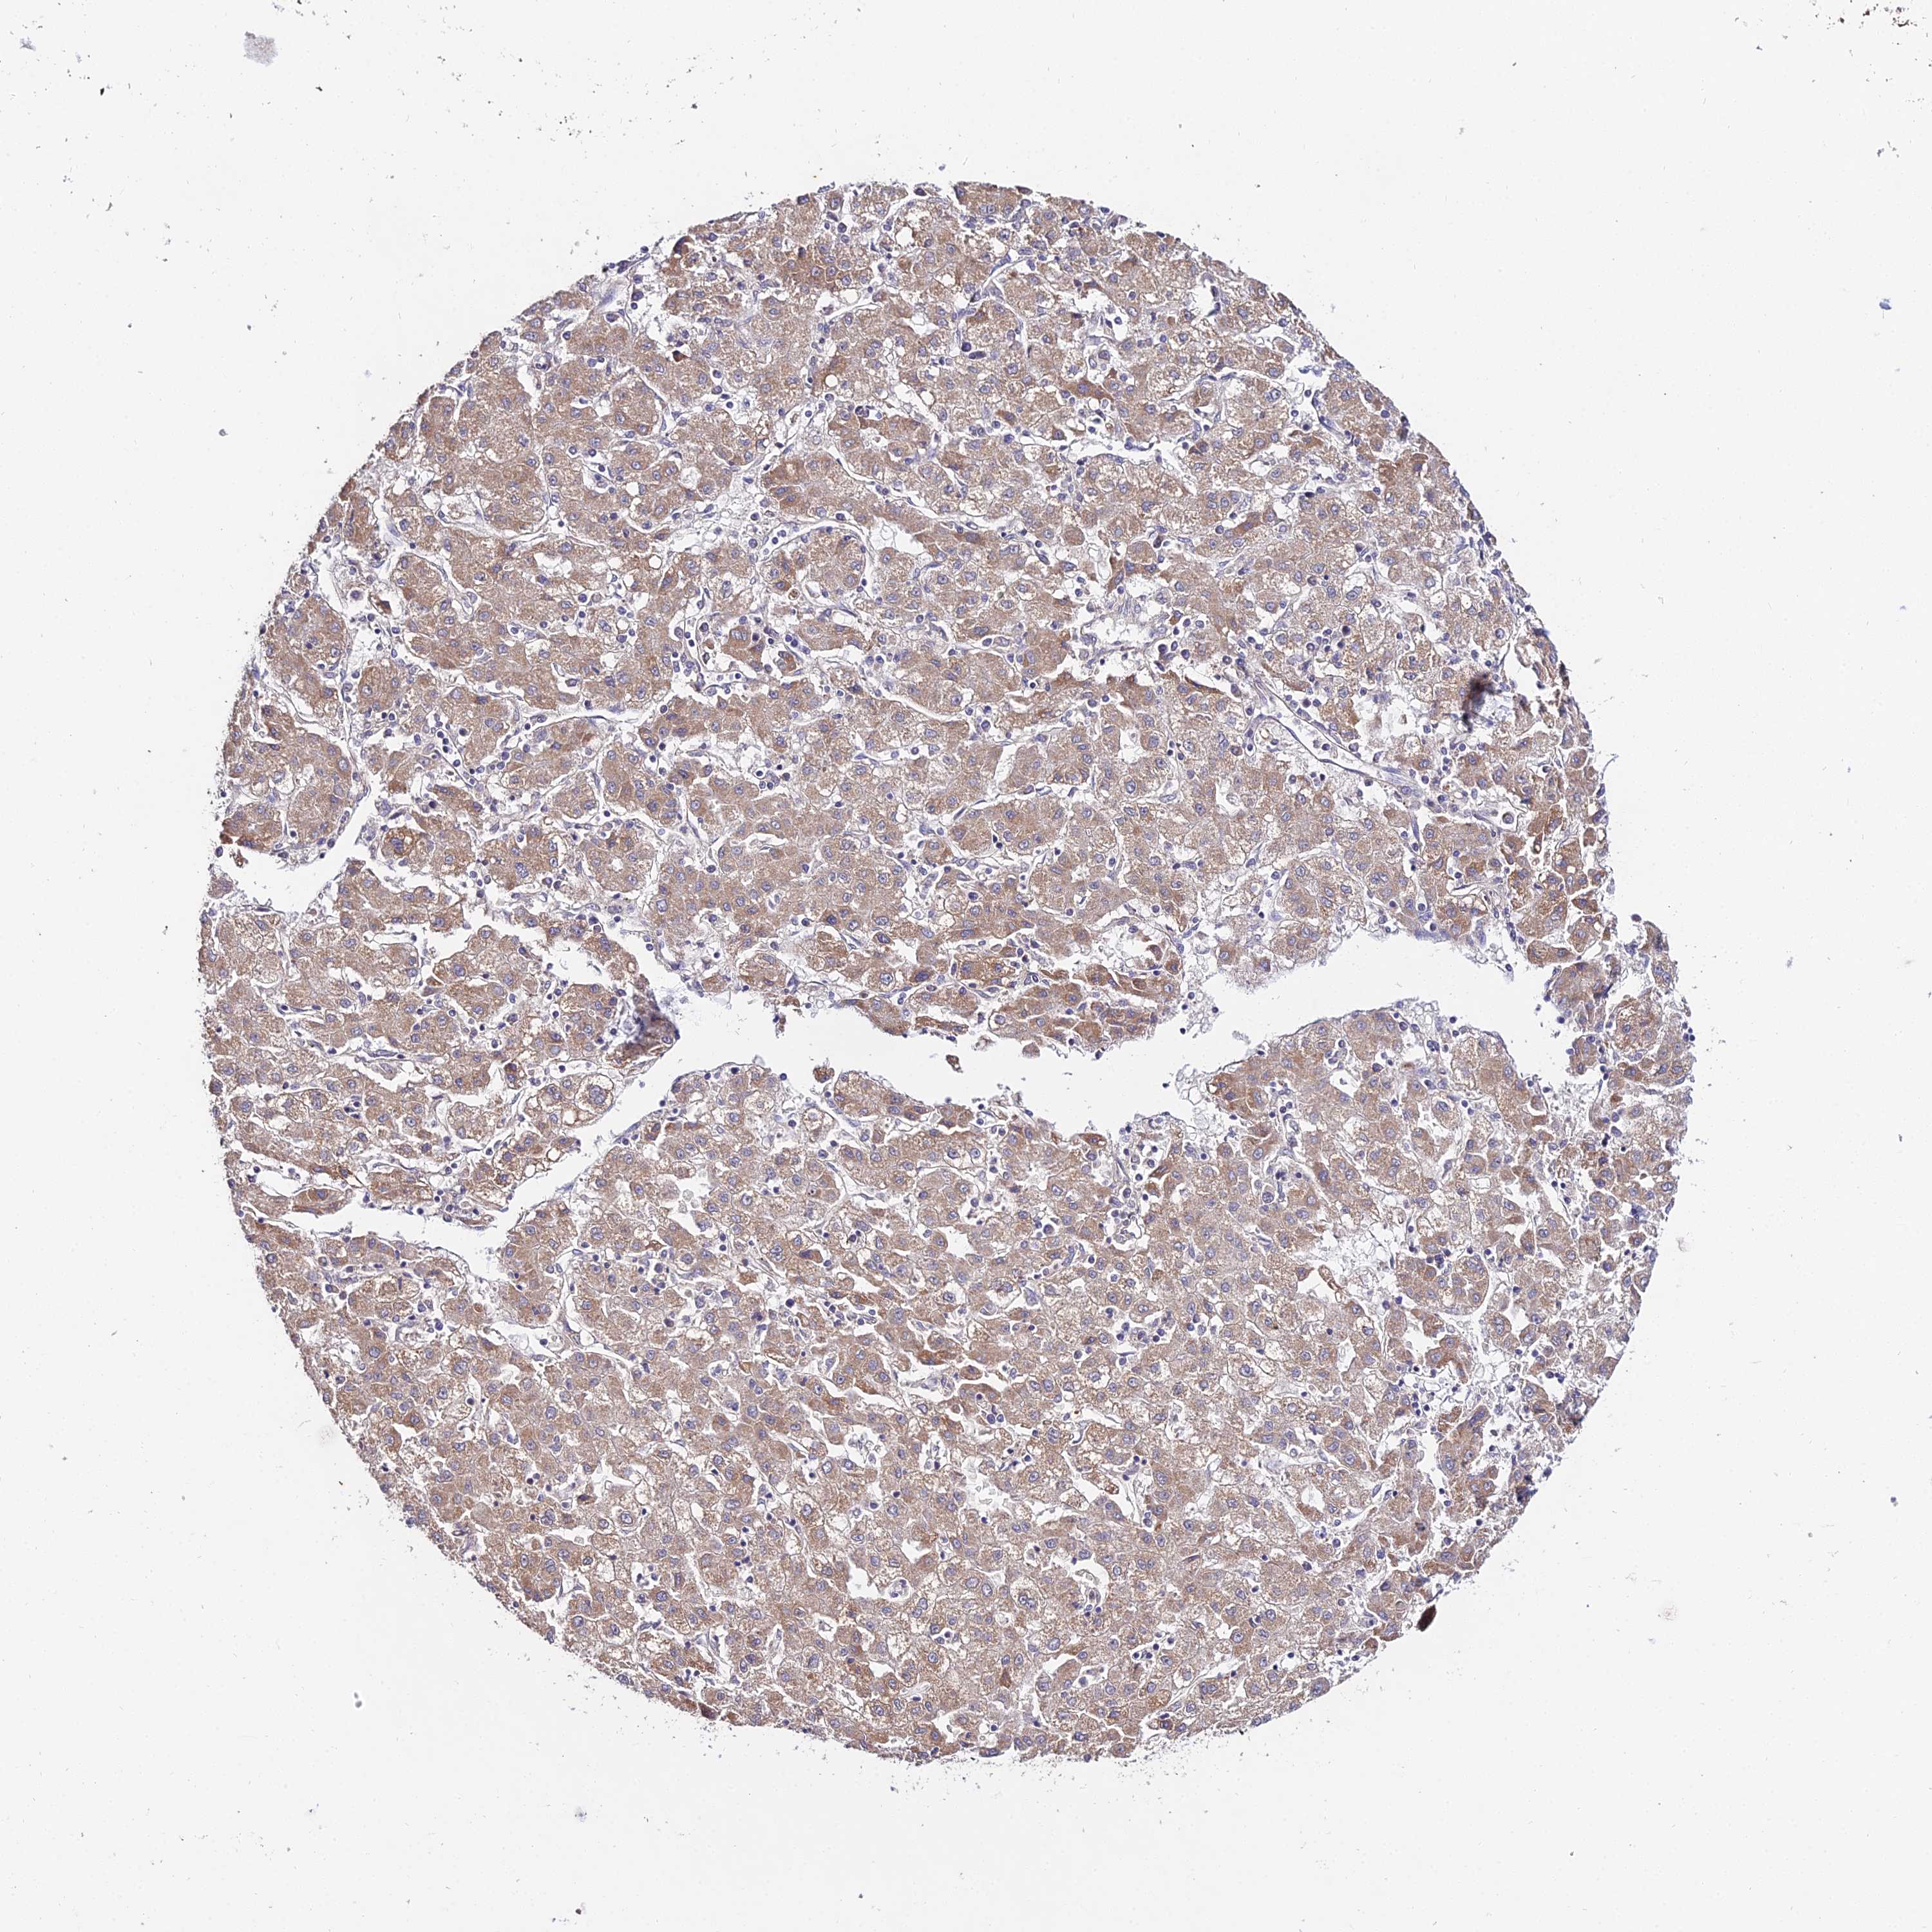

LIVER CANCER - Protein expressioni

A mouse-over function shows sample information and annotation data. Click on an image to view it in a full screen mode. Samples can be filtered based on level of antibody staining by selecting one or several of the following categories: high, medium, low and not detected. The assay and annotation is described here.

Note that samples used for immunohistochemistry by the Human Protein Atlas do not correspond to samples in the TCGA dataset.

Antibody stainingi

Antibody staining in the annotated cell types in the current human tissue is reported as not detected, low, medium, or high, based on conventional immunohistochemistry profiling in selected tissues. This score is based on the combination of the staining intensity and fraction of stained cells.

Each image is clickable and will lead to virtual microscopy that enables deeper exploration of all samples and also displays staining intensity scores, fraction scores and subcellular localization as well as patient and tissue information for each sample.

Antibody HPA042994

Staining

High

Medium

Low

Not detected

Intensity

Strong

Moderate

Weak

Negative

Quantity

>75%

75%-25%

<25%

None

Location

Nuclear

Cytoplasmic/membranous

Cytoplasmic/membranous,nuclear

Cholangiocarcinoma

Carcinoma, Hepatocellular, NOS